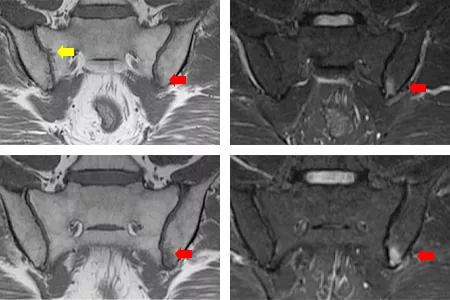

単純X線では仙腸関節の明らかな骨びらんは明らかではなかったが、内転筋や臀部筋の付着部の”けば立ったcalcification像”がみられ脊椎関節炎が疑われた。その後仙腸関節MRI(斜位冠状断 T1強調画像およびSTIR撮影)を行ったところ、左仙腸関節にT1強調画像でlow、STIR画像でHighの活動性仙腸関節炎をみとめ、T1強調画像では右仙腸関節に骨びらんもみとめられた(写真5)。

写真5 仙腸関節MRI(斜位冠状断)T1強調画像およびSTIR画像

連続する3スライスにてT1強調画像 low STIR画像 highの骨髄浮腫を認めた(赤矢印)

T1強調画像にて骨びらんあり(黄色矢印)